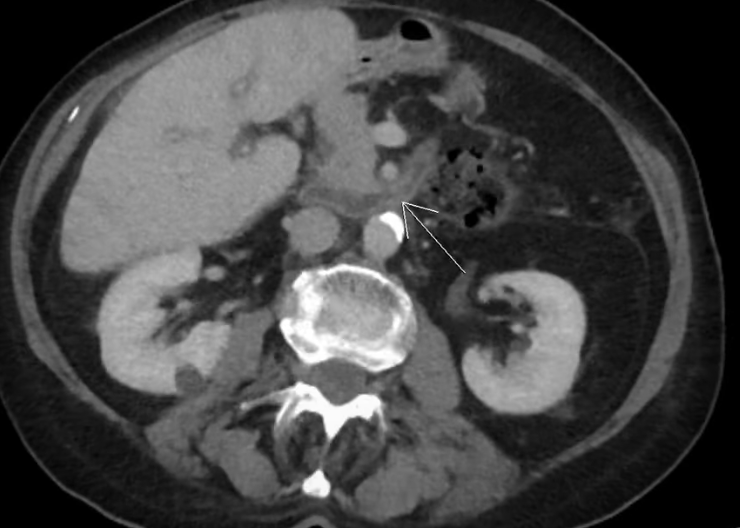

CAZ nr 101 Tumoră vezicală

Discuţie caz nr 101: În cazul hematuriei, indicația este de CT abdomen și pelvis cu substanță de contrast și achiziție în timp excretor (uroCT). Peretele vezicii urinare poate avea grosime crescută datorită unor procese de tip inflamator sau datorită creșterii presiunii în fața unui obstacol (creșterea de volum a prostatei de exemplu). La această pacienta în urmă cu 2 ani se observă o creștere a grosimii peretelui, dar nu numai în zona unde actual se dezvoltă o tumoră vezicala, fără a se individualiza o priză de contrast localizată în timp arterial. Pentru stadializare locală a unei tumori vezicale (invazia muscularei) examinarea IRM are acuratețe mai bună decât examinarea CT.

NB Pacienta avea în antecedente o intervenție chirurgicală pentru inel duodenal și pe examinare se mai pune în evidență un defect de perete abdominal paramedian stâng periombilical la nivelul căruia, în decubit dorsal, evoluează grăsime abdominală.

DE LUAT ACASĂ!!! Creșterea grosimii peretelui vezical este evaluată optim cu vezica plină și trebuie evaluată prezența unei prize de contrast parcelare în timp arterial.